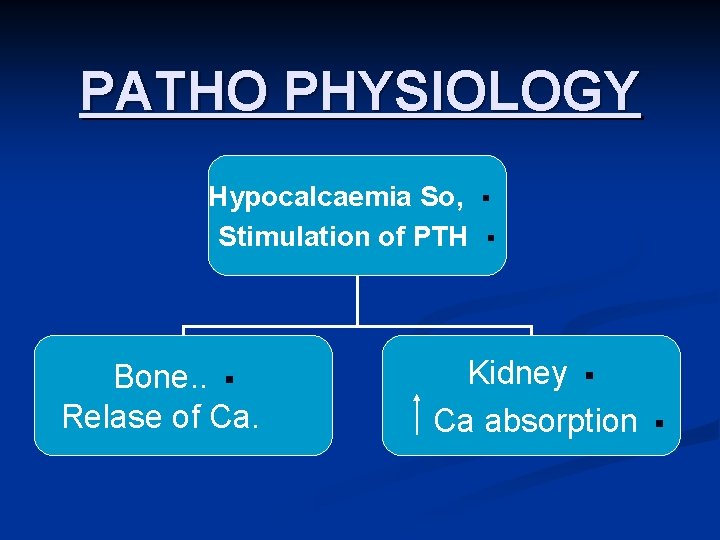

PATHO PHYSIOLOGY Hypocalcaemia So, Stimulation of PTH Bone. . § Relase of Ca. § § Kidney § Ca absorption §